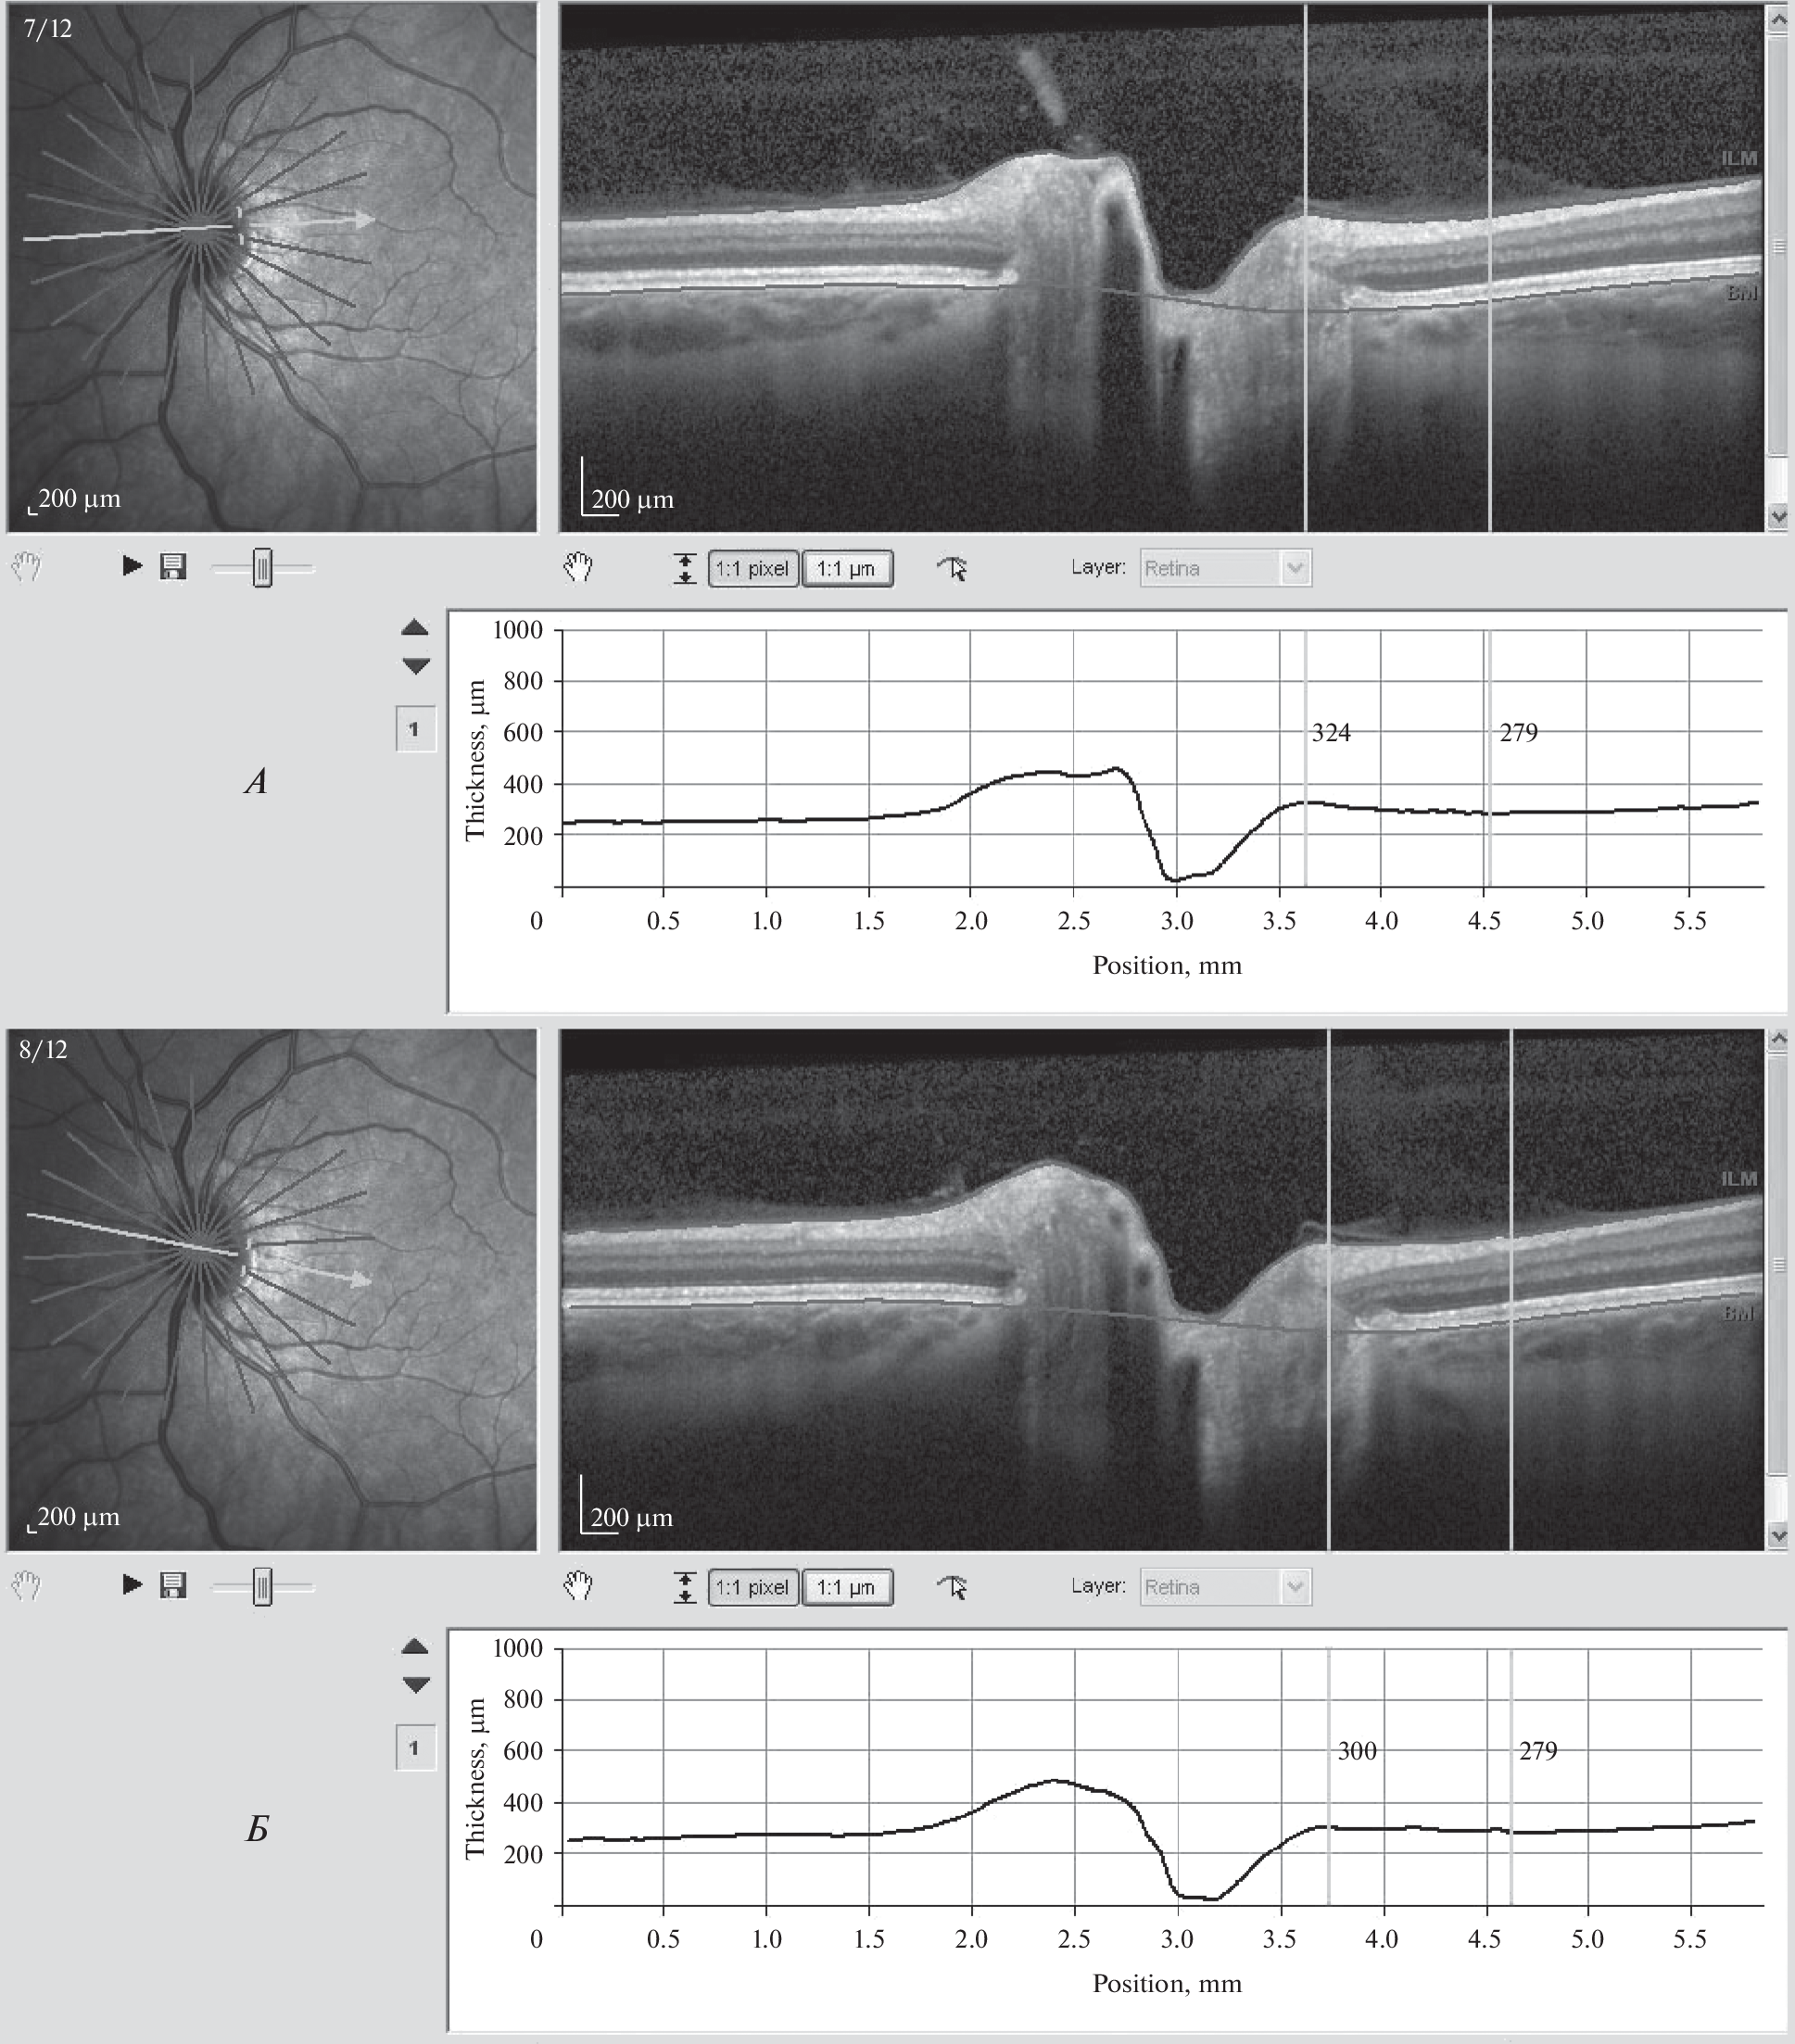

The article analysis the state of 24 eyes of 12 Russian cosmonauts who made long-term space flights to the ISS in the period from 2016 to 2021. The analysis was carried out by HRA and OCT images study, using the Display function included in the program of Spectralis OCT device. The thickness of the optic nerve head and retina was determined according to the hourly meridians, which allowed us to accurately diagnose and classify the optic disc edema according to the stages of the Frisen scale. By measuring the percentage ratio of the maximum thickness of the nerve disc within its boundaries to the minimum thickness of the retina outside the boundaries of the disc, we determined the digital value of prominence in each temporal hourly meridian, limited by the temporal sector of 95°. The presence of prominence in the extreme temporal meridians, or its absence at all, we regarded as a physiologically healthy state of the optic disc, corresponding to stage 0. This stage was established in 13 eyes (54.2%). Stage I (7 eyes (29.2%)) was diagnosed based on the absence of prominence in the horizontal temporal meridian. The defining feature of stage II is an increase in prominence in the temporal horizontal meridian by more than 10%. Subclinical stage II (prominence is increased, but less than 10%) was diagnosed in two eyes of two cosmonauts (8.3%). Clinically pronounced papilledema II–III stages was diagnosed in two eyes (8.3%) in one cosmonaut, where the maximum value of prominence was 70.1% in the right eye, and on the left – 40.1% in the horizontal meridian. The study shows that an increase in prominence up to 70% in the temporal horizontal meridian at stage III of edema leads to neurodegeneration of the optic nerve fibers in space flight. At stages II–III of edema, an increase in the minimum thickness of the neuroretinal rim compared with all other observations. At 0 – II subclinical stage, according to this indicator, it was impossible to differentiate the state of the optic disc.